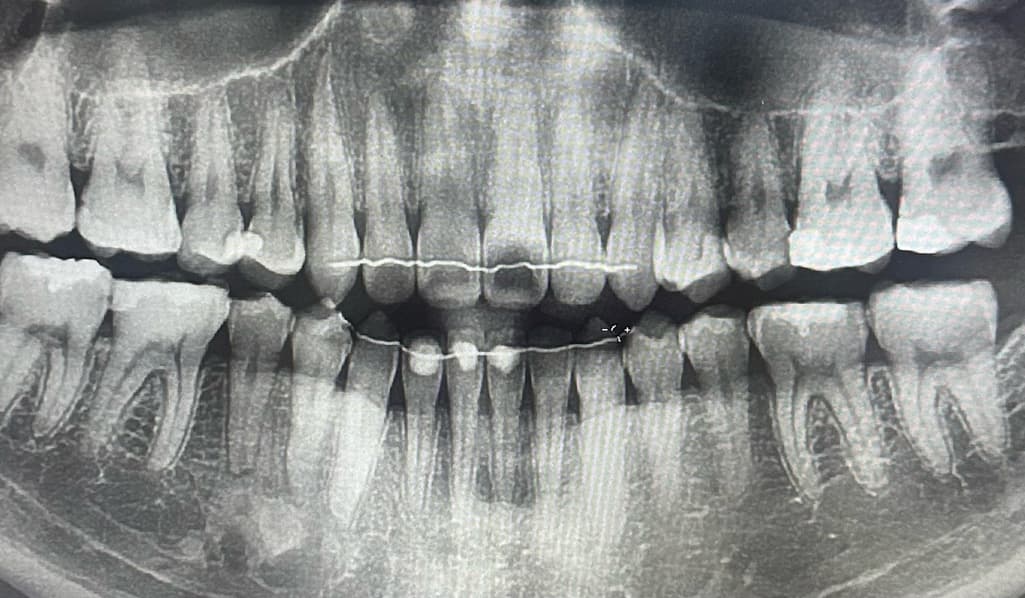

치아 신경 손상??이라는 진단을 받았는데 맞을까요?

치아가 가만히 있을때는 안아프고, 뭐 먹거나 씹으면 통증이 있습니다. 신경치료를 하라고 말을 하던데 가만히 있을때는 아프지 않은데 신경치료를 하야할까요?

사진으로만 봤을 경우에는 큰 충치가 보이진 않습니다. 하지만 치아에 금이가 있거나 했다면 해당 부위가 음식을 먹을 때 불편할 수 있습니다. 금이 생겼다면 정상적인 치아라고 하더라도 과도한 힘에의해 통증이 느껴질 수 있으니 치아의 가해지는 힘을 줄여주는 것이 좋습니다.